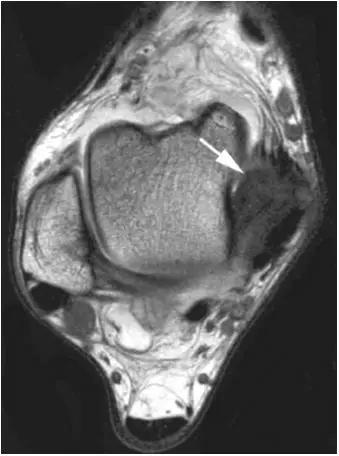

影像学表现为距骨胫骨间肌腱及趾长屈肌腱水肿、增厚,内踝及距骨后内侧骨赘形成。

轴位示意图示后内侧撞击综合征:M:内踝;L:外踝;TP:胫后肌腱;FDL:趾长屈肌腱;Talus:距骨。短箭:距骨胫骨间肌腱深层纤维;箭头:距骨胫骨间肌腱后部纤维。

X线平片示胫骨后部骨赘形成,MR质子像黑箭示胫骨内后侧骨赘形成,白箭示内后侧软组织增厚, 白箭头:胫后肌腱;黑箭头:趾长屈肌腱